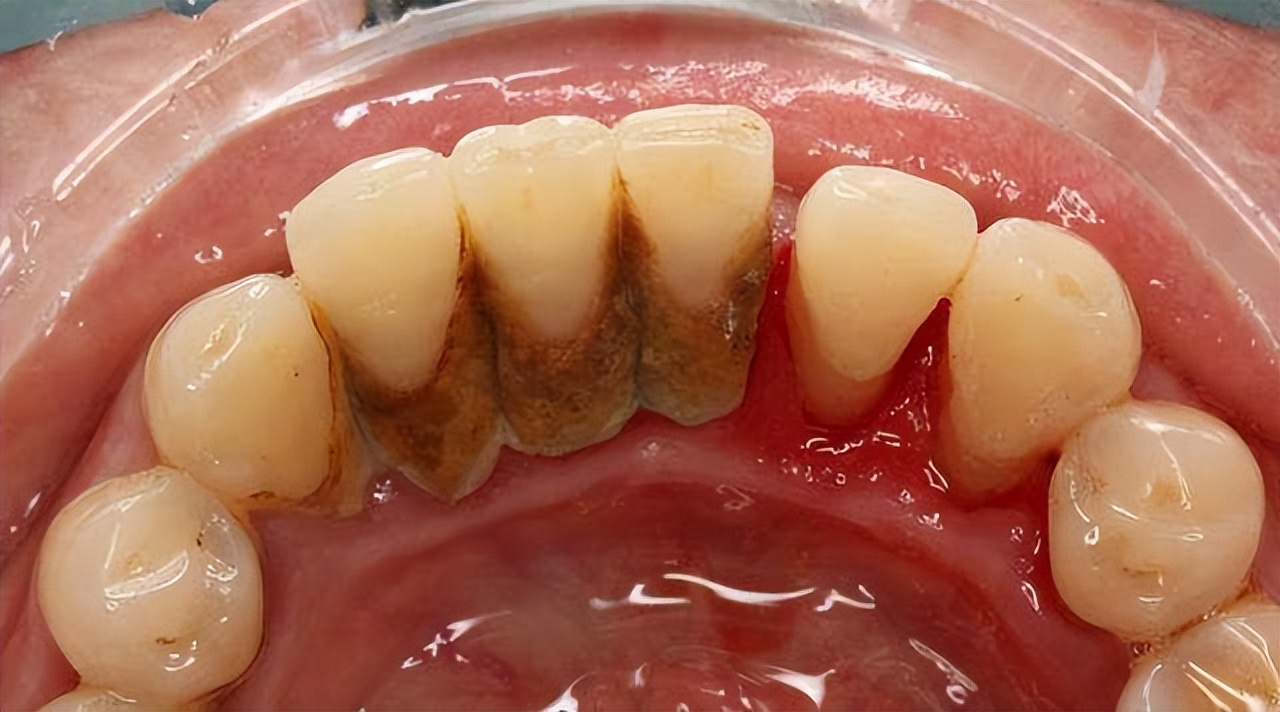

牙结石附着在牙冠或者牙齿的颈部,主要是由食物残渣物,口腔上皮细胞和唾液中的矿物质脱落和脱落形成的钙化矿物质形成。

牙结石颜色是白色或者黄色,如果吸烟会慢慢变成黑色,主要分为上牙龈结构和龈下结石。

牙结石附着在牙齿表面是已经钙化的硬性沉积物,一般刷牙很难清除,多呈浅黄色,但常常可因饮食、喝茶、吸烟以及药物等因素导致染色加深,对牙齿美观造成了极大的不利影响。

牙结石是附着在牙齿表面的硬性斑块,其外形似黄色干石灰块,较坚硬,牙结石容易吸附细菌和毒素,再加上牙结石本身局部刺激很容易导致牙龈出血。